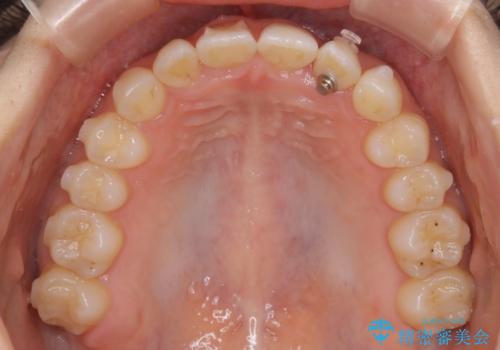

- 前から2番目の歯が捻じれていることが気になるとご相談にいらした方です。

インビザラインFULLで治療を行いました。

上の前から2番目の歯は、一般的に周囲の歯と比べて小さく、動きづらい歯であると言われています。前歯にゴムかけを行うことで理想的な位置まで歯を動かしてくることが出来ました。